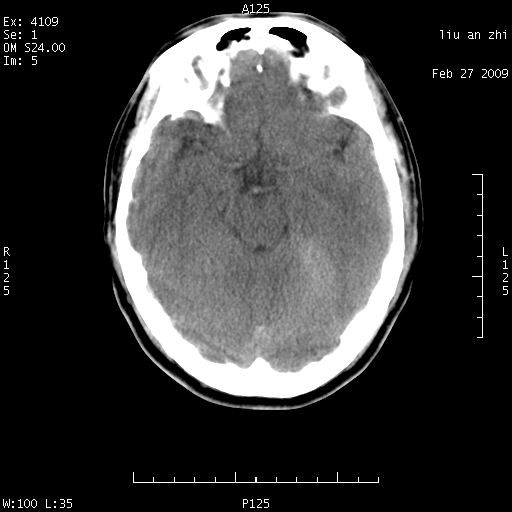

患者:男,32岁 被打伤后3天,自感头昏头痛作头颅ct检查。请大家看一下想什么??

请注意小脑幕!!!

考虑左侧天幕硬膜下血肿。

左侧天幕硬膜下血肿

ct18448的结果:mri检查左侧天幕下血肿

以下是引用深蓝一号在2009-3-9 16:22:00的发言:[br]ct18448的结果:mri检查左侧天幕下血肿。